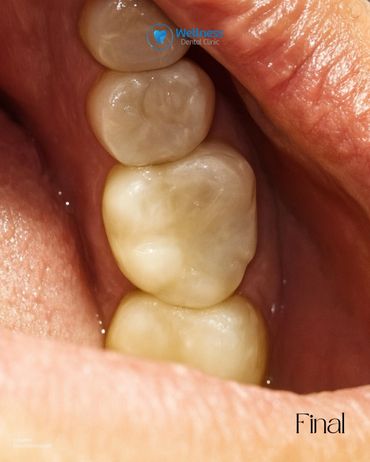

En Wellness Dental Clinic utilizamos tecnología de última generación para ofrecer restauraciones precisas, estéticas y duraderas. 🦷💙 Este procedimiento se realizó en un solo día, con una duración aproximada de dos horas. 🔹 Proceso realizado: 1. Preoperatoria – Evaluación inicial de la pieza. 2. Preparación – Eliminación de caries y conformación del diente. 3. Diseño digital en CEREC – Modelado personalizado de la incrustación. 4. Fresado – Fabricación de la restauración en cerámica de alta resistencia. 5. Prueba y ajuste – Revisión de puntos de contacto y adaptación. 6. Cementado – Colocación definitiva. 7. Pulido final – Integración estética y natural. 8. Resultado final – Función y estética recuperadas. Cada paso fue realizado bajo protocolos de precisión y seguridad, logrando un resultado completamente personalizado para nuestro paciente. ✨ 📲 Agenda tu valoración y descubre la experiencia Wellness. 📍 Independencia #1118 – Local 12, Piso 4, Zona Urbana Río Tijuana 📞 664 208 9300 | 📱 WhatsApp: 664 477 4313 🌐 wellnessdentalclinic.us 📧 wellnessdentalclinictj@gmail.com